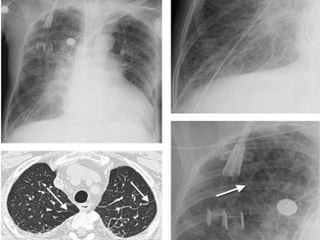

This 50-year-old man presented with end-stage lung fibrosis

PA chest radiograph shows medium to coarse reticular

B: CT scan shows multiple small cysts (honeycombing) involving

predominantly the subpleural peripheral regions of lung. Traction

bronchiectasis, another sign of end-stage lung fibrosis.

b. Reticular Pattern Areticular pattern results from the summation or superimposition of irregular linear opacities. The term reticular is defined as meshed, or in the form of a network. Reticular opacities can be described as fine, medium, or coarse, as the width of the opacities increases. A classic reticular pattern is seen with pulmonary fibrosis, in which multiple curvilinear opacities form small cystic spaces along the pleural margins and lung bases (honeycomb lung)

• 178.

This 50-year-old manpresented with end-stage lung fibrosis PA chest radiograph shows medium to coarse reticular B: CT scan shows multiple small cysts (honeycombing) involving predominantly the subpleural peripheral regions of lung. Traction bronchiectasis, another sign of end-stage lung fibrosis.